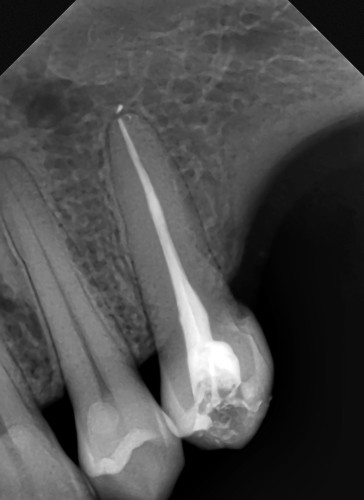

Can Antibiotics Heal an infected Root Canal? All you need to know East Orange Endodontics Can Antibiotics Help A Root Canal Infection the use of antibiotics is intended to control the infection and relieve symptoms, potentially delaying the need for a root canal. antibiotics can control infection symptoms but may not eliminate the source of the problem. Root canals involve removing infected pulp, addressing the core issue to prevent recurrence. can antibiotics heal an infected root canal? If the. Can Antibiotics Help A Root Canal Infection.